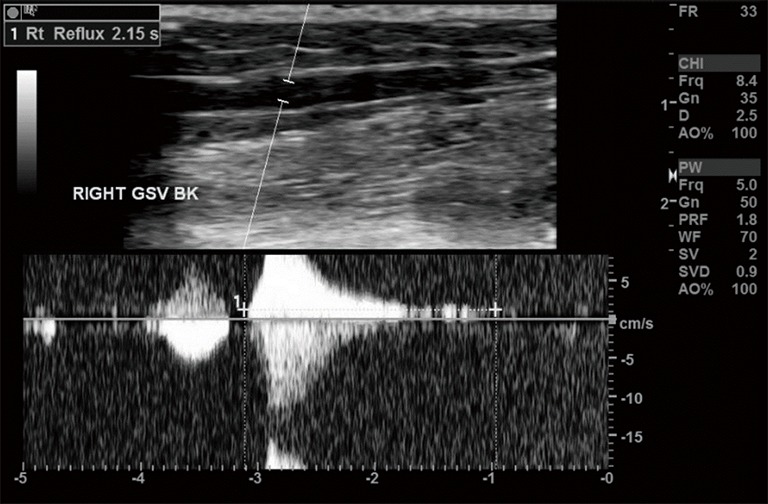

Figure 4.

Venous duplex ultrasound demonstrating reflux in the right greater saphenous vein. Blood flow direction is determined after increasing central venous return with rapid cuff inflation then deflation. Flow in the direction of the feet is because of incompetent valves. The Doppler spectrum quantifies the duration of reflux, and in the example above it is ~2.15 seconds.